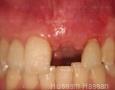

Pictures

Surgery